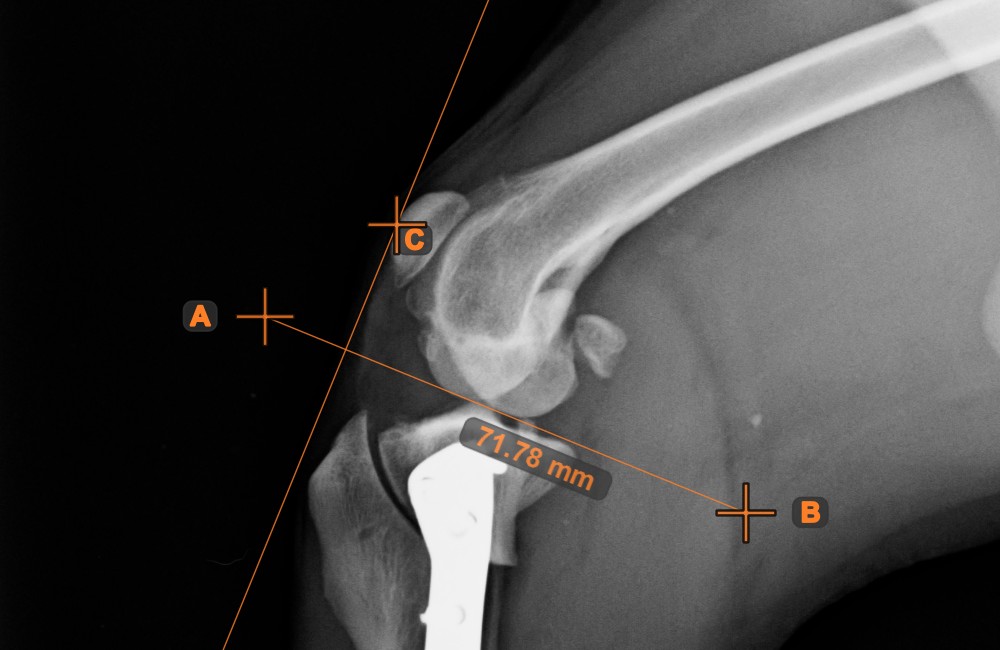

Center Point of Line¶

Identify and mark the center point of a new or existing line measurement on the scene by using the Center Point of Line tool.

Select the tool from the left toolbar and assign it to one of the available mouse buttons. Place the start and end points on the scene, select them from already existing points on the image, or select an already drawn line from the scene. The center point of the line will be automatically calculated and placed on the scene. The center point of each line will always be marked with the letter C.